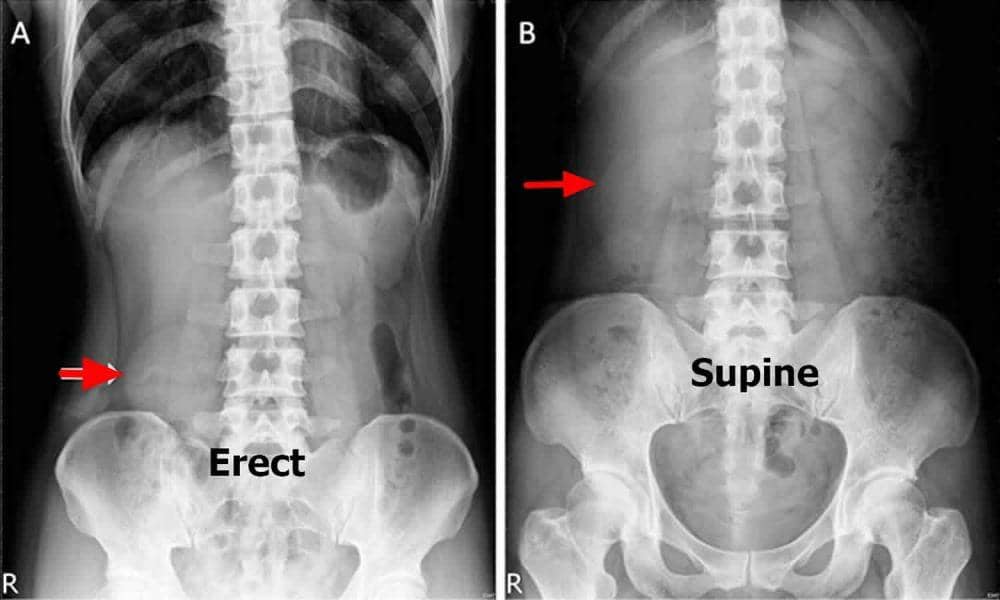

Tes harus dilakukan ketika orang tersebut berbaring dan berdiri. Lewat gambar, seseorang dengan nefroptosis akan dengan jelas menunjukkan ginjal turun sekitar 5 cm.